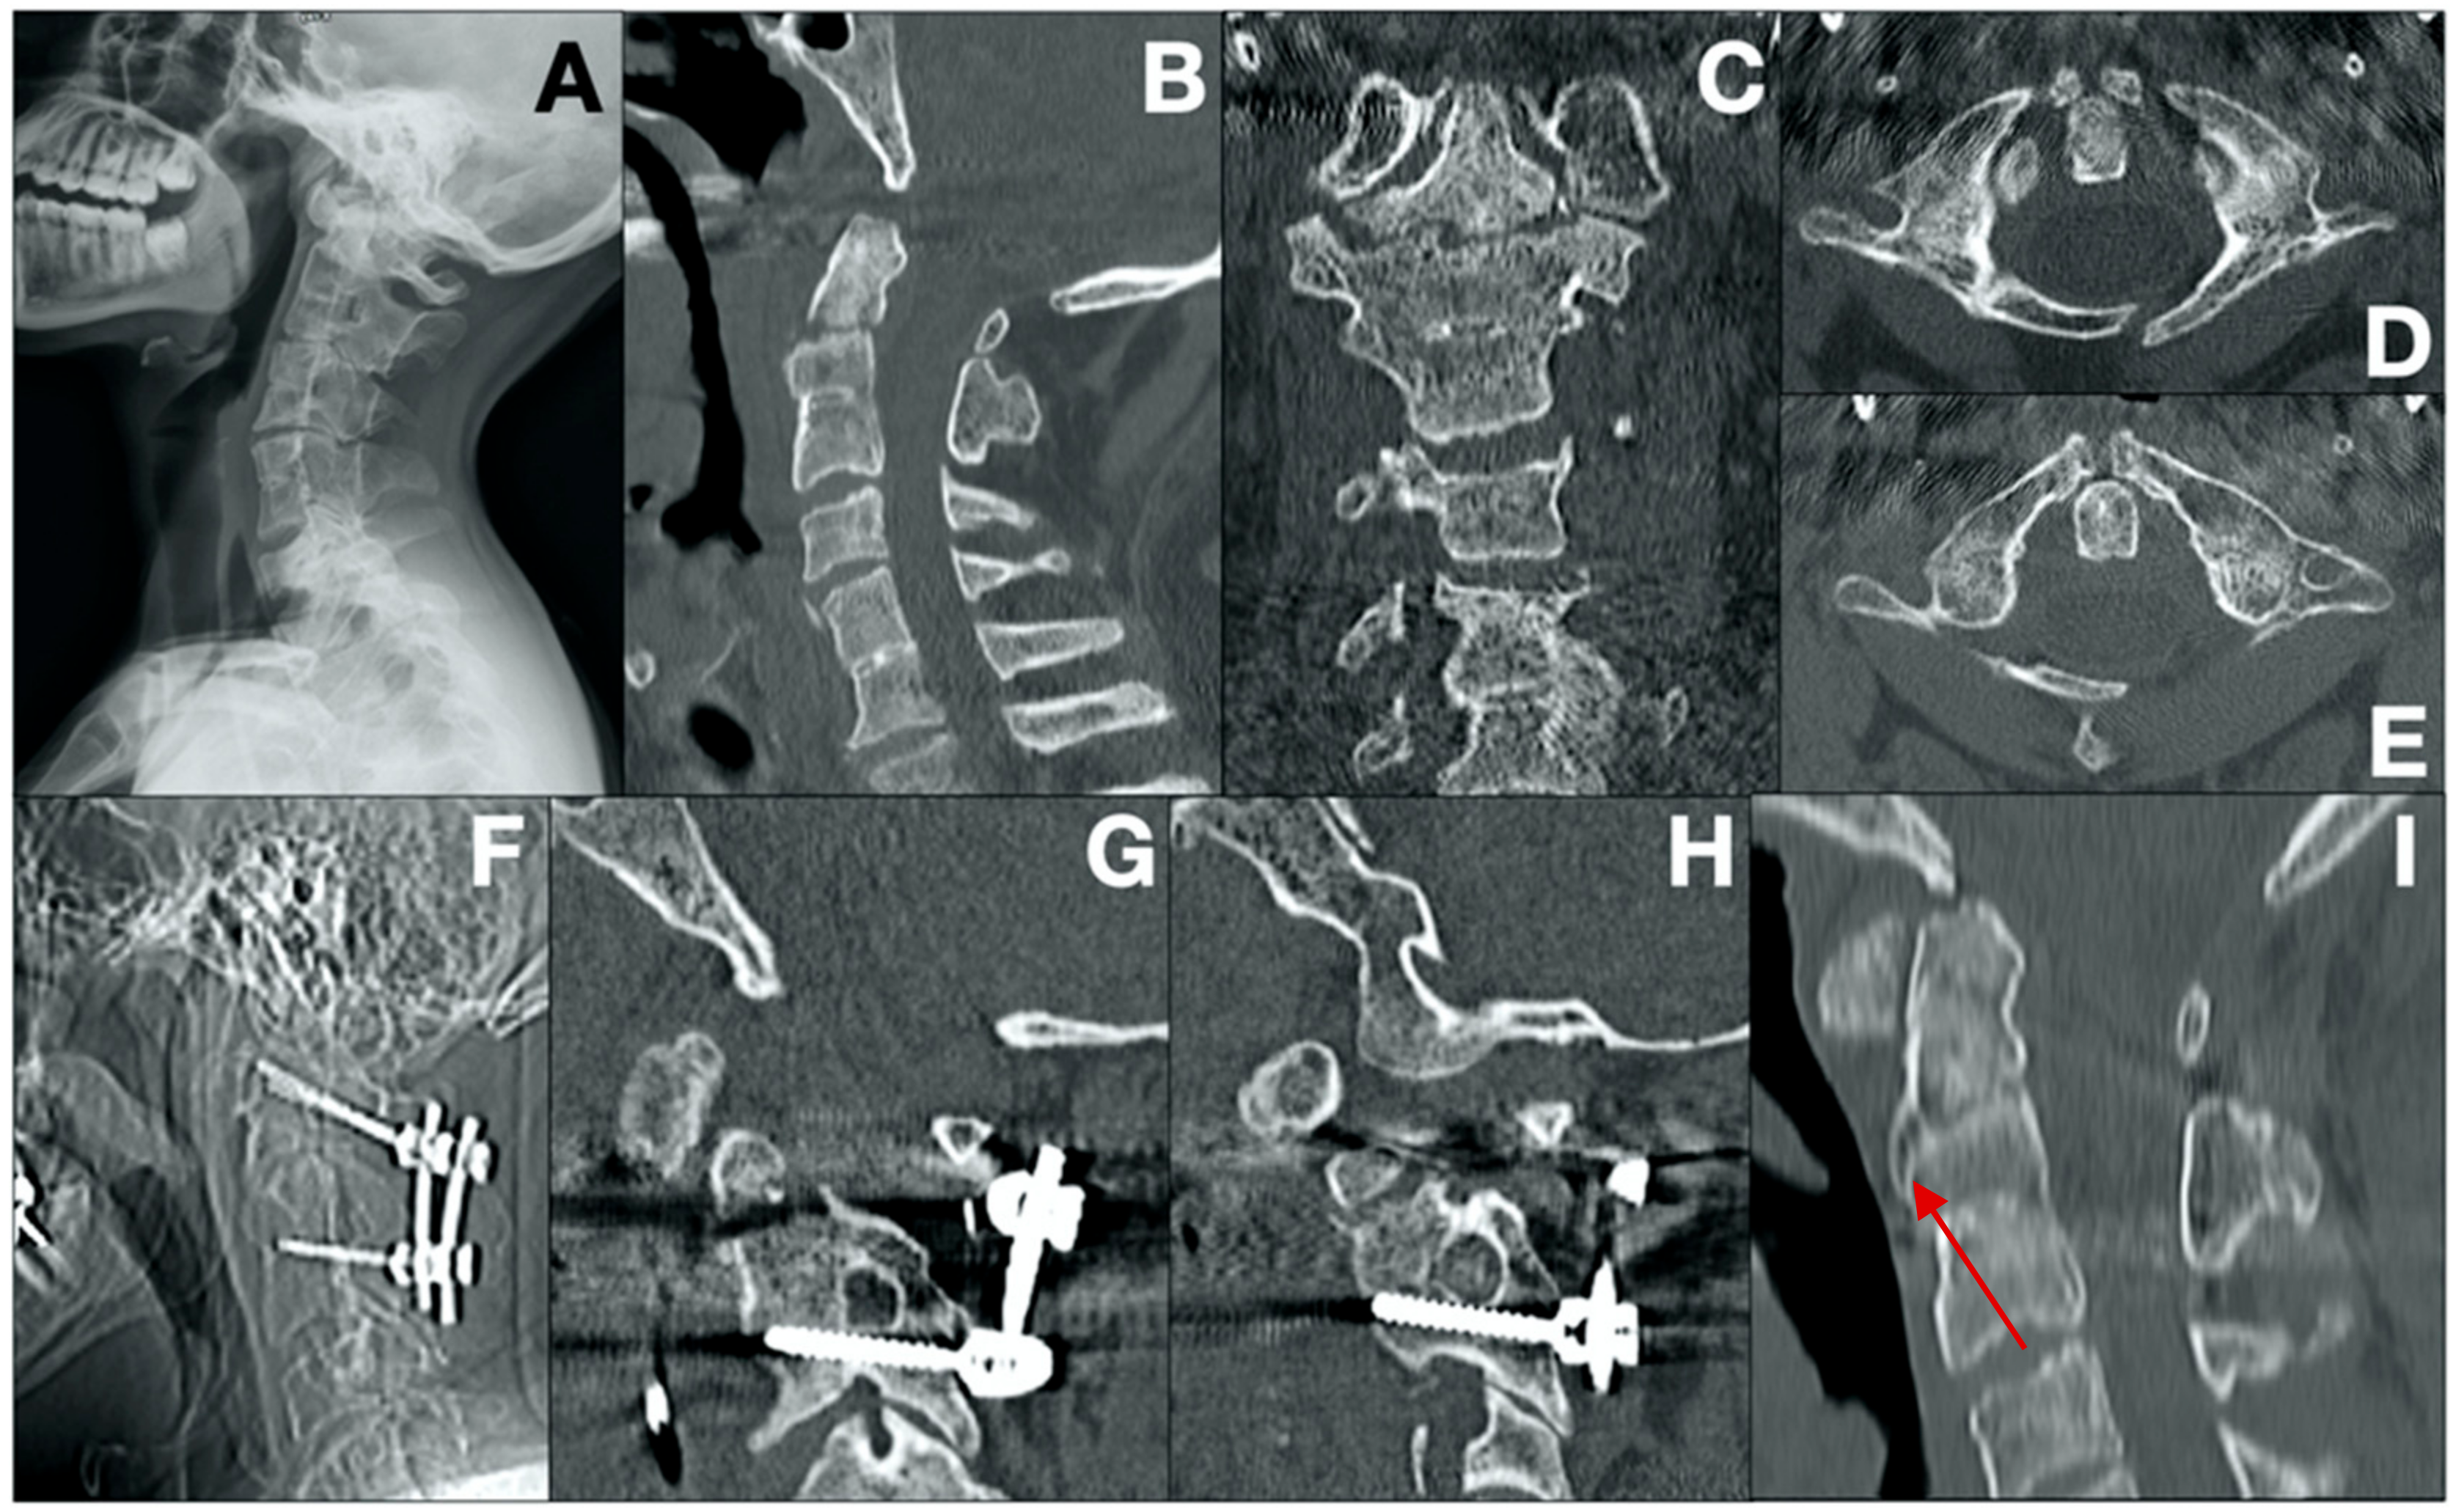

- Case 2 (Figure 2)